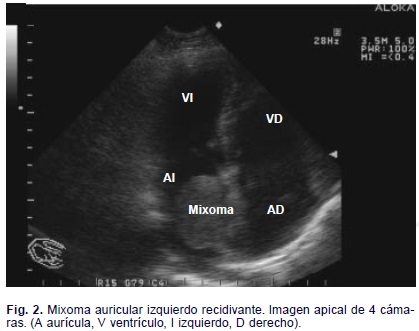

Después de 2 años de seguimiento postquirúrgico, la paciente, abandonó la consulta por sentirse bien y acudió nuevamente, 6 meses después, refiriendo disnea de esfuerzo, edema en miembros inferiores y astenia. Al examen físico encontramos escasos estertores crepitantes bibasales y ligero edema que ascendía hasta el tercio inferior de ambas piernas. La auscultación cardiovascular reveló un soplo basal II/VI, audible también en el ápex, compatible con esclerosis del aparato valvular aórtico. El electrocardiograma fue normal. indicamos exámenes humorales y radiológicos y encontramos los primeros normales, la radiografía de tórax postero-anterior no mostraba cardiomegalia, pero existía ligero edema intersticial hacia las bases y el ecocardiograma transtorácico reveló la presencia de una masa sésil de 25 x 32 mm adosada a la cara izquierda del septum interauricular que ocupaba alrededor del 60% de la cavidad auricular izquierda (Figs. 1, 2, y 3).